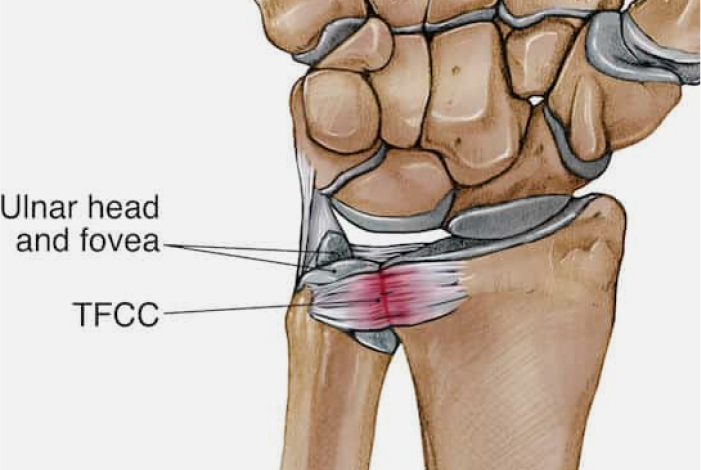

손목의 자측(새끼손가락 쪽)에 위치한 연골복합체(TFCC)는

손목의 안정성을 유지하고 충격을 흡수하는 중요한 구조물입니다.